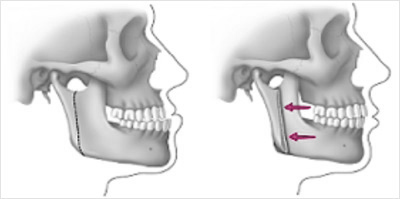

Correcting a protrusive lower jaw (protruding) consists in separating a posterior section from the anterior section (which contains the teeth). It is then placed (moved back) into the optimal position for aesthetics and function.